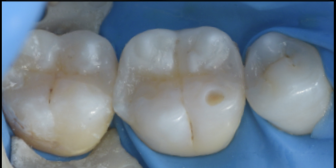

【40代 女性】

詰め物が劣化した

- 担当医

- 生野 誠

- 主訴

- 詰め物が劣化した

虫歯になってないか不安

- 期間

- 1回

- 費用

- 7万

- 治療内容

- ダイレクトボンディング

- 治療に伴うリスク

- コンポジットレジンの劣化